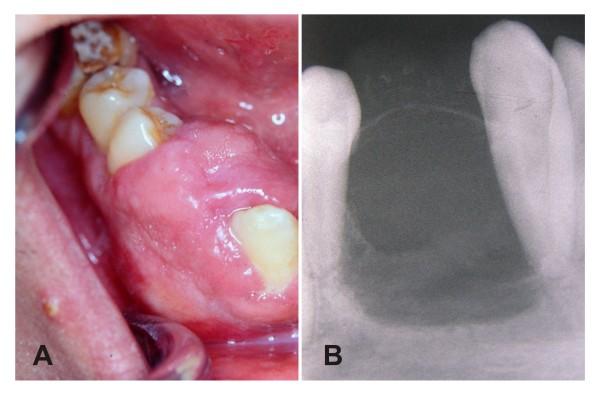

An osteolytic tumour of the mandible with prominent expansive growth on the alveolar ridge and displacement of the involved teeth is described in a 28-year-old man. The lesion was diagnosed as a central odontogenic fibroma, an uncommon benign neoplasm derived from dental apparatus, and was removed by curettage. The patient remains asymptomatic after thirteen years of follow-up, which supports the claimed indolent behavior of this poorly documented disease and the adequacy of a conservative surgical treatment.

一位 28 岁男性患者的下颌出现溶骨性肿瘤,表现为牙槽嵴明显膨胀性生长和受累牙齿移位。该病变被诊断为中央性牙源性纤维瘤,一种源自牙器的罕见良性肿瘤,通过刮除术进行切除。十三年随访后患者无症状,这支持该疾病罕见且惰性的特征,以及保守手术治疗的充分性。